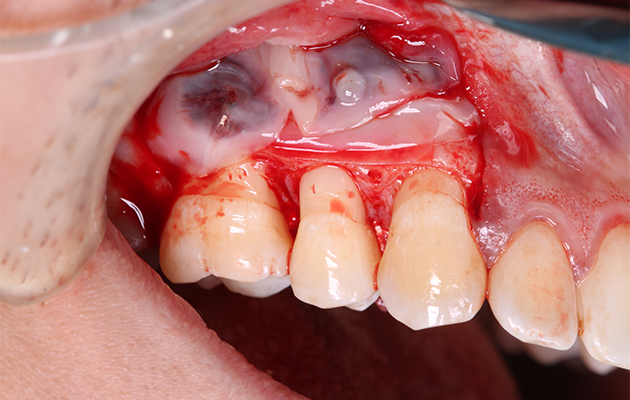

16 | Membranas de L-PRF comodadas sobre a membrana sintética.

17 | Síntese.